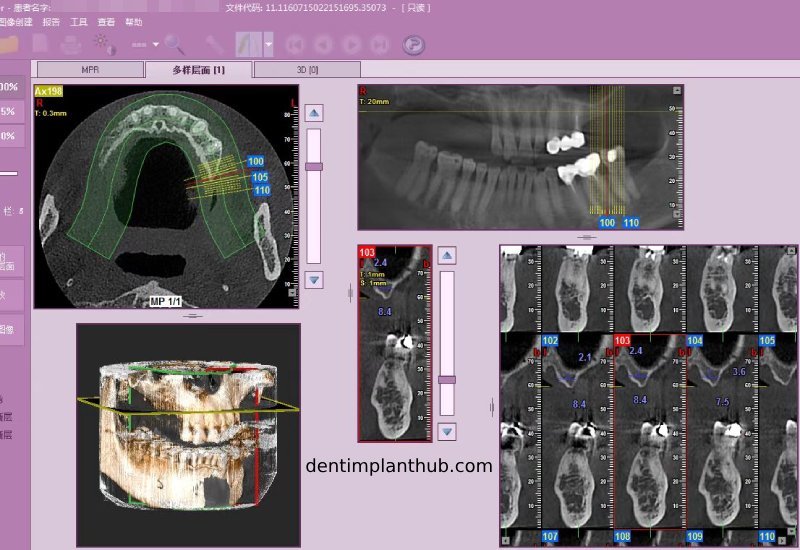

Screenshot of patient's CT on March 14, 2024